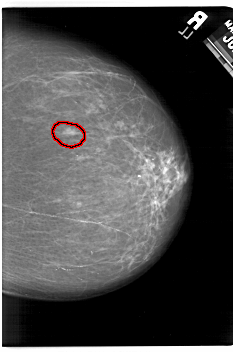

A_1532_1.LEFT_CC

LEFT_CC LINES 6541 PIXELS_PER_LINE 4441 BITS_PER_PIXEL 12 RESOLUTION 43.5 NON_OVERLAY

FILE: A_1532_1.RIGHT_CC.OVERLAY

TOTAL_ABNORMALITIES 1

ABNORMALITY 1

LESION_TYPE MASS SHAPE OVAL MARGINS ILL_DEFINED

ASSESSMENT 4

SUBTLETY 3

PATHOLOGY MALIGNANT

TOTAL_OUTLINES 1

BOUNDARY